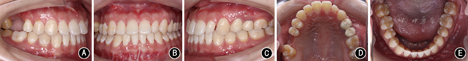

患者女性,21岁。主诉:"地包天",面部不美观,要求改善面型。否认家族史。

患者正面观基本对称,面下1/3略长。侧面凹面型,鼻旁区凹陷,下颌前突。口内检查:左右侧磨牙完全近中关系;前牙轻度开

1.5 mm,覆盖-4.0 mm;上牙列拥挤,下牙列舌向倾斜无拥挤。上中线右偏2.0 mm,下中线右偏2.5 mm。X线检查示上颌后缩下颌前突。头影测量显示SNA角77.56°,SNB角81.87°,ANB角-4.31°,Wits值17.93 mm,L1/MP角72.12°。

安氏Ⅲ类错

畸形,毛氏Ⅱ1+Ⅳ2;骨性Ⅲ类,上颌后缩下颌前突。

详细向患者阐述手术提前方案与传统术前正畸方案的优缺点及治疗风险后,患者选择手术提前方案并签署知情同意书。拼对模型后发现,该患者不存在明显的手术

干扰点,故直接行正颌手术纠正骨性不调。术前粘贴矫治器,置入0.356 mm(0.014英寸)镍钛圆丝作为正畸初始弓丝。转正颌外科行下颌双侧升支矢状劈开术。术中全麻下于上下颌前牙区及后牙区行种植体支抗植入术。术后2周去除颌间牵引,术后4周去除咬合板后行术后正畸。术后种植体支抗颌间牵引预防复发。术后正畸25个月,总疗程26个月。

覆盖正常。全口曲面体层X线片示牙根排列基本平行。患者对早期即解决主诉感到满意,治疗前后头颅侧位X线片及头影描迹重叠图见

像;B:正面

像;C:左侧

像;D:上颌

面像;E:下颌

面像